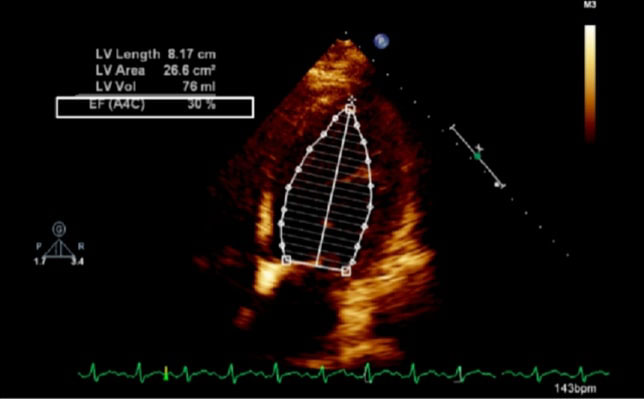

The exemption from the Institutional Review Board of Cleveland Clinic and consent from the patient were obtained for our case. A 42-year-old obese (body mass index 37.6 kg/m2) female at 38w2d, G2P1 with past medical history significant for gestational diabetes mellitus, presented with a three-day history of shortness of breath, orthopnea, chest tightness, tachycardia, headache, and swollen feet. She denied fever, vision changes, and right upper abdominal pain. No history of cardiac diseases or chronic hypertension was reported. Her vital signs included blood pressure (BP) of 145/98 mmHg, respiratory rate of 30 breaths per minute, heart rate of 150 beats per minute (bpm), and blood oxygen saturation (SpO2) of 98% on 10 liters per minute of oxygen through a non-rebreather mask. She was afebrile. Physical exam revealed loud S3 gallop, bilateral basilar rhonchi, and bilateral feet and ankle edema. Fetal monitoring was normal with a heart rate of 125 bpm. Laboratory results showed a white blood cell count of 12.8 k/µL, urine protein of 74 mg/dl, NT-proBNP of 1017 pg/ml, mildly elevated aspartate transaminase of 45 U/L and alanine transaminase of 30 U/L, and normal troponin. Electrocardiogram reported sinus tachycardia with borderline LV hypertrophy and frequent premature ventricular contractions (PVCs). Chest X-ray showed bilateral basilar infiltration. Echocardiogram revealed dilated LV with severely decreased function, EF of 25%, diffuse LV hypokinesia, and normal right ventricle function (Figure 1 and Figure 2). The patient started contractions and labor analgesia was administered through the epidural catheter; BP was noted to be 118/62 mmHg. Coagulation profile was normal. She was admitted to the intensive care unit (ICU) and Swan Ganz catheter, central, and arterial lines were inserted to monitor hemodynamics and heart function. Although our patient's clinical symptoms may lead us to consider preeclampsia, we ruled out preeclampsia because her labs did not meet criteria for diagnosis. Our patient was diagnosed with PPCM, for which she was placed on intravenous (IV) furosemide, tocolytic medication, and digoxin. Tocolytic medication was given to delay delivery until heart function improved, as the patient was unable to lie flat and EF was very low.

Figure 2: Echocardiogram of apical four chamber view of the heart, depicting left ventricular wall hypertrophy (white arrow).